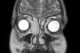

Ethmoid sinus cancer

The ethmoid sinuses or ethmoid air cells of the ethmoid bone are one of the four paired paranasal sinuses. The cells are variable in both size and number in the lateral mass of each of the ethmoid bones and cannot be palpated during an extraoral examination. [Source: Wikipedia ]